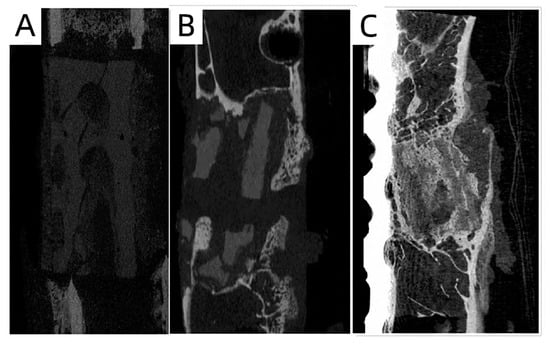

3.4. In Vivo Animal Experiments